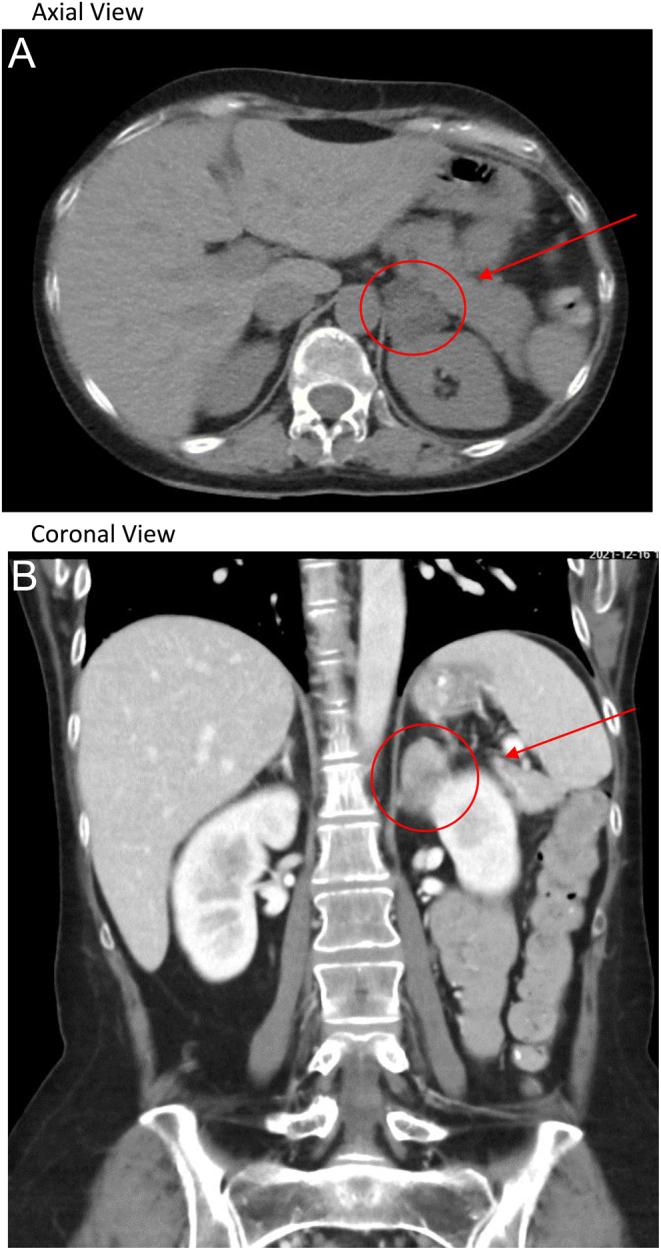

Menstrual cycle abnormalities are common in premenopausal females with Cushing's syndrome, although the underlying mechanism is poorly understood. Signs and symptoms found in Cushing's syndrome overlap with polycystic ovarian syndrome (PCOS). The patient is a 33-year-old female previously diagnosed by a gynecologist with PCOS and treated with oral contraceptive pills (OCPs) for 2 years. She then discontinued her OCPs without consulting a clinician, resulting in amenorrhea for 6 months, for which she presented. She also had symptoms of depression and anxiety but had no other signs and symptoms of Cushing's syndrome, except a plethoric face. Initial lab work showed evidence of central hypogonadism (low luteinizing hormone, follicle-stimulating hormone, and estrogen), so a complete anterior pituitary hormone workup was done. Her thyroid-stimulating hormone was also low with a low free T4 level. Prolactin level was normal, but surprisingly, her AM cortisol level was high. The Cushing's syndrome workup revealed non-suppressed cortisol after a 1 mg dexamethasone suppression test and positive 24-h urine cortisol with suppressed adrenocorticotrophic hormone. A CT scan of her adrenal glands revealed a left adrenal adenoma. She underwent a left adrenalectomy, after which her menstrual cycles became regular again, and pituitary function has recovered.

尽管潜在机制尚不清楚,但月经周期异常在绝经前库欣综合征女性中很常见。库欣综合征的体征和症状与多囊卵巢综合征(PCOS)重叠。该患者为33岁女性,此前被妇科医生诊断为PCOS,并口服避孕药(OCPs)治疗2年。之后她未咨询临床医生就自行停用了OCPs,导致闭经6个月,遂前来就诊。她还有抑郁和焦虑症状,但除了面色潮红外,没有库欣综合征的其他体征和症状。初始实验室检查显示有中枢性性腺功能减退的证据(促黄体生成素、促卵泡生成素和雌激素水平低),因此进行了完整的垂体前叶激素检查。她的促甲状腺激素也低,游离T4水平也低。催乳素水平正常,但令人惊讶的是,她的上午皮质醇水平高。库欣综合征检查显示,1毫克地塞米松抑制试验后皮质醇未被抑制,24小时尿皮质醇阳性且促肾上腺皮质激素被抑制。肾上腺CT扫描显示左侧肾上腺腺瘤。她接受了左侧肾上腺切除术,术后月经周期恢复正常,垂体功能也已恢复。